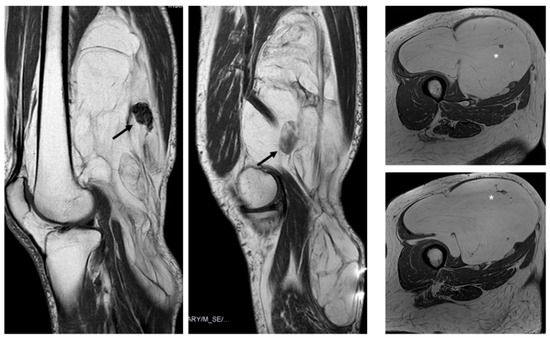

Fifty-four of the 59 lipomas had not septa or septa < 2 mm, while nineteen of 20 ALT had septa and these were ≥2 mm in 38%, (p value = 0.001) (Figure 2).

Figure 2.

Sagittal T1W (A) and axial T2W (B) and DP SPAIR (C) MR images with a heterogeneous lipomatous mass (arrows) in the anterior compartment of the left thigh. The final diagnosis was atypical lipomatous tumor (ALT) confirmed as MDM2 positive.

The presence and thickness of septa show significant differences between lipomas and ALTs. This one agrees with the findings of Kransdorf and Hosono, where the septa were thick and irregular in ALT/WDL and thin in lipoma [12,16]. Similarly, Brisson observed that lipomas were isointense to subcutaneous fat and may contain a few thin septa [17]. In our series, the absence of septa indicates lipoma and septa ≥ 2 mm is suggested of ALT. Septa < 2 mm can be indicative of either lipoma or ALTs (Figure 5).

Figure 5.

Septations. Coronal T1W image (A) showing a lipomatous tumor (black arrows) with thin septa < 2 mm (arrowhead) in the gluteal region. Final diagnosis: lipoma (MDM2 negative). Sagittal T1W image (B) showing a lipomatous tumor (black arrows) with thick septa ≥ 2 mm (open arrowhead). Final diagnosis: atypical lipomatous tumor (MDM2 positive).